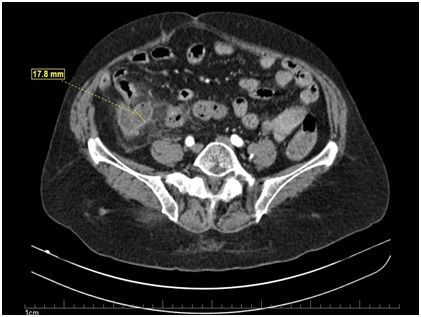

Ultrasonography of total abdomen performed on the day of care without alterations. Computed tomography showed a distended, thickened appendix with adjacent adipose densification, with no associated perforationor collection signs, suggesting a diagnosis of appendicitis (Figure 1). Anexploratory laparotomy was indicated for possible appendectomy.

Figure 1: Computed Tomography (CT) of sagittal incidence evidencing a distended appendix, thickened with adjacent adipose densification.